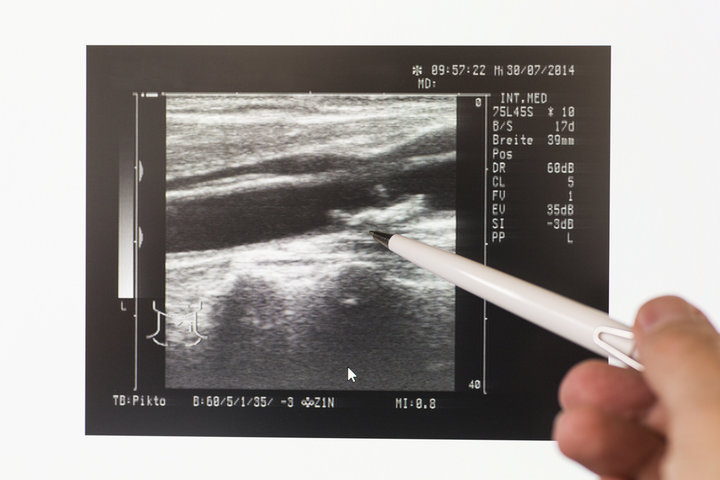

경동맥 초음파 검사 방법

- 검사 준비: 편안한 자세로 눕고 목 부위를 노출합니다.

- 젤 도포: 초음파 신호 전달을 돕기 위해 피부에 젤을 바릅니다.

- 초음파 탐촉자 사용: 의료진이 탐촉자로 혈관 내부를 확인하며 혈류 상태를 측정합니다.

- 검사 시간: 약 15~30분 정도 소요되며, 통증 없이 진행됩니다.